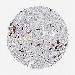

PROSTATE CANCER - Protein expressioni

A mouse-over function shows sample information and annotation data. Click on an image to view it in a full screen mode. Samples can be filtered based on level of antibody staining by selecting one or several of the following categories: high, medium, low and not detected. The assay and annotation is described here.

Antibody stainingi

Antibody staining in the annotated cell types in the current human tissue is reported as not detected, low, medium, or high, based on conventional immunohistochemistry profiling in selected tissues. This score is based on the combination of the staining intensity and fraction of stained cells.

Each image is clickable and will lead to virtual microscopy that enables deeper exploration of all samples and also displays staining intensity scores, fraction scores and subcellular localization as well as patient and tissue information for each sample.

Antibody HPA001860

Antibody CAB013108

Staining

High

Medium

Low

Not detected

Intensity

Strong

Moderate

Weak

Negative

Quantity

>75%

75%-25%

<25%

None

Location

Nuclear

Cytoplasmic/membranous

Cytoplasmic/membranous,nuclear

Adenocarcinoma, Medium grade

Adenocarcinoma, High grade

Adenocarcinoma, Low grade